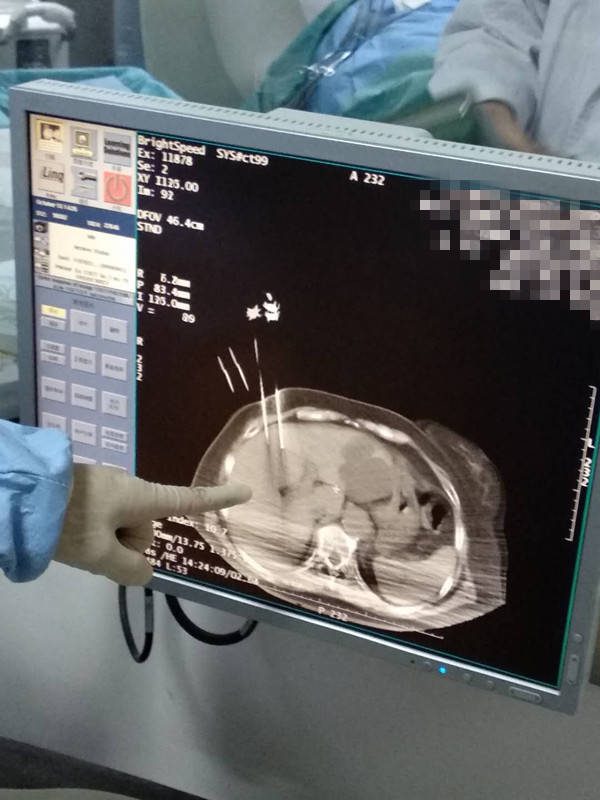

73岁患者肝部氩氦刀冷冻消融

发布人:美国氩氦刀技术官方网站    发布时间:2020/10/16 16:15:21